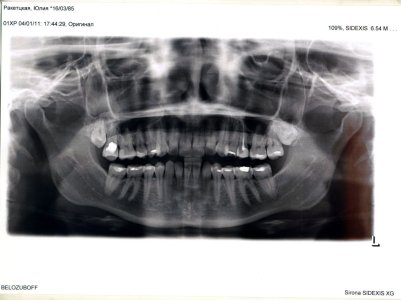

Ситуация такая. Внезапно разболелся зуб. Боль пульсирующая, резко усиливающаяся при надавливании на зуб. Первый день полоскала содой, на второй боль поутихла, но я все равно пошла к стоматологу сделать рентген (до этого полгода назад была, все было в порядке). Врач мне не понравилась. Сказала, что надо удалить зубы мудрости, которые не вылезли, иначе, якобы, потом с ними будет то же, что и сейчас с больным зубом. Говорит, вскрылся свищ и гной выходит, поэтому боль стихает. На мой вопрос, как там хоть не периодонтитная ситуация, она сказала, да периодонтит уже давно, так периодически и будет обостряться, если не удалить, мол, неправильно запломбированы каналы (зуб делали очень много лет назад, никогда не было никакого обострения). В общем я сразу удалять не стала, взяла паузу и снимок. Скажите, если я выложу снимок, вы сможете что-либо сказать по поводу больного зуба? Спасибо.